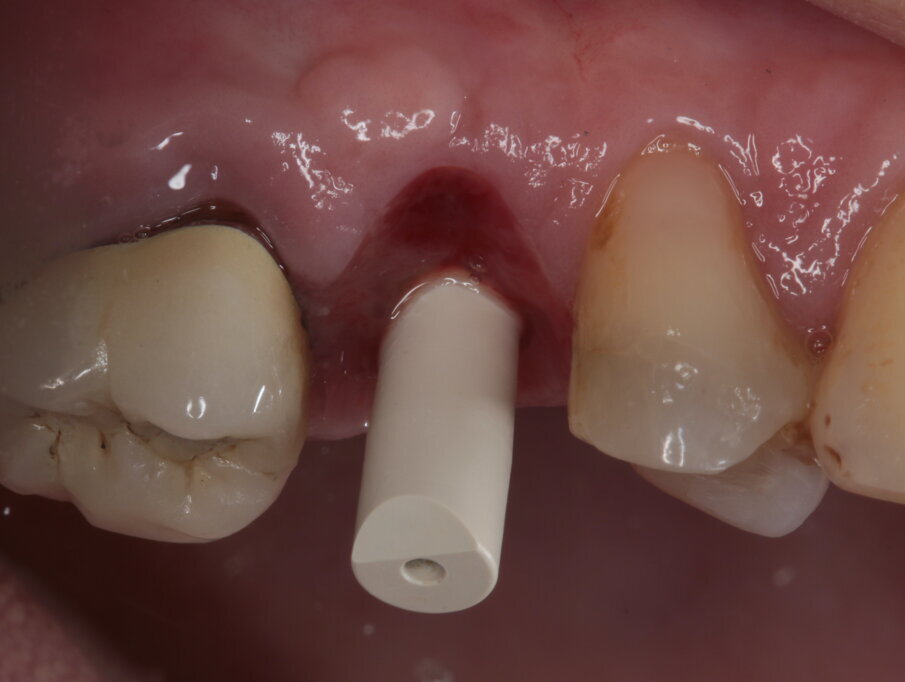

Viene disegnato un roll flap, posizionato l’impianto tramite una mascherina di guida per la fresa pilota ottenuta tramite stampa 3D, inserita una vite di guarigione transmucosa e suturato il lembo. Dalle immagini intraoperatorie si può notare come la scelta di materiale a rapido riassorbimento abbia permesso l’ottenimento di un osso vitale, sanguinante e con la quasi totale assenza di particelle di biomateriale ancora presenti. L’imprecisione nella sutura della porzione distale del lembo genererà uno spessore maggiorato del connettivo in quella zona, che avrà come effetto un piccolo inestetismo che tuttavia la paziente non nota e che non intende correggere (Figg. 14-17). Al termine dei 4 mesi necessari al completamento del processo di osteointegrazione, viene inserito un provvisorio avvitato con il quale inizia il condizionamento dei tessuti perimplantari.

Nelle prime fasi questo avrà un profilo ovviamente non compatibile con quello di un restauro definitivo, ma molto utile per ottenere una compressione sul connettivo ormai maturo che migrerà verso vestibolare e verso coronale (Figg. 18-21). Dopo tre mesi, nei quali il provvisorio viene progressivamente ridotto nella sua componente vestibolare seguendo la risposta dei tessuti, e la paziente costantemente monitorata nel mantenimento della sua igiene orale, viene rilevata l’impronta tramite scanner ottico (Figg. 22-24) e consegnato il definitivo avvitato in zirconia, con un profilo ancora più ridotto e a questo punto ideale anche per il mantenimento igienico (Figg. 25-28).